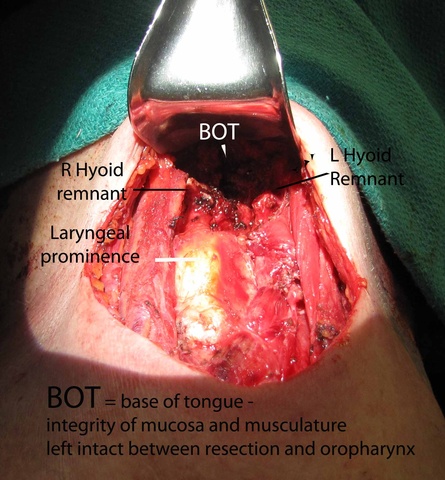

The hyoid bone was identified with preservation of soft tissue about the central portion and isolation of the bone laterally. On the right side, just medial to the lesser cornua and used a Freer underneath to protect while we released the hyoid with the mighty bite. The left side was addressed in identical fashion, except that we were lateral to the lesser cornua. The dissection was carried superiorly with a cuff of muscle.

From above, surgeon reached into the mouth and palpated the foramen cecum with the left hand and arm protected with a sterile sleeve and second glove - placed to permit later removal from the contaminated oral cavity to permit continued sterile dissection in a sterile field. With anatomic control directed by palpation intra-orally with concurrent dissection of the open neck, clips were placed to mark the region of the undersurface of the base of tongue where the TGD cyst was to be severed. Final cuts with the bovie were similarly directed both by intra-oral palpation and extra-oral inspection.

Frozen section was taken from the superior most part of the tract - revealing no evidence of a tract. Had there been a tract identified, further dissection (potentially communicating intraorally) would have been done where the hemoclips had been placed above the hyoid (see also: Case example thyroglossal duct cyst with tract through to oropharynx.)

Clinical Images